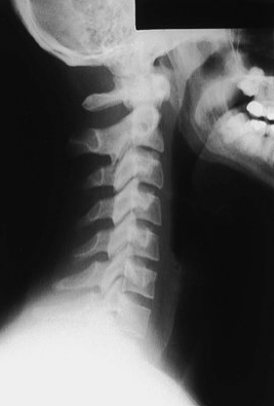

What view is this? What is it great for viewing?

AP open-mouth

Odontoid fx

Lateral Csp

Best for disc space and facet joint orientation